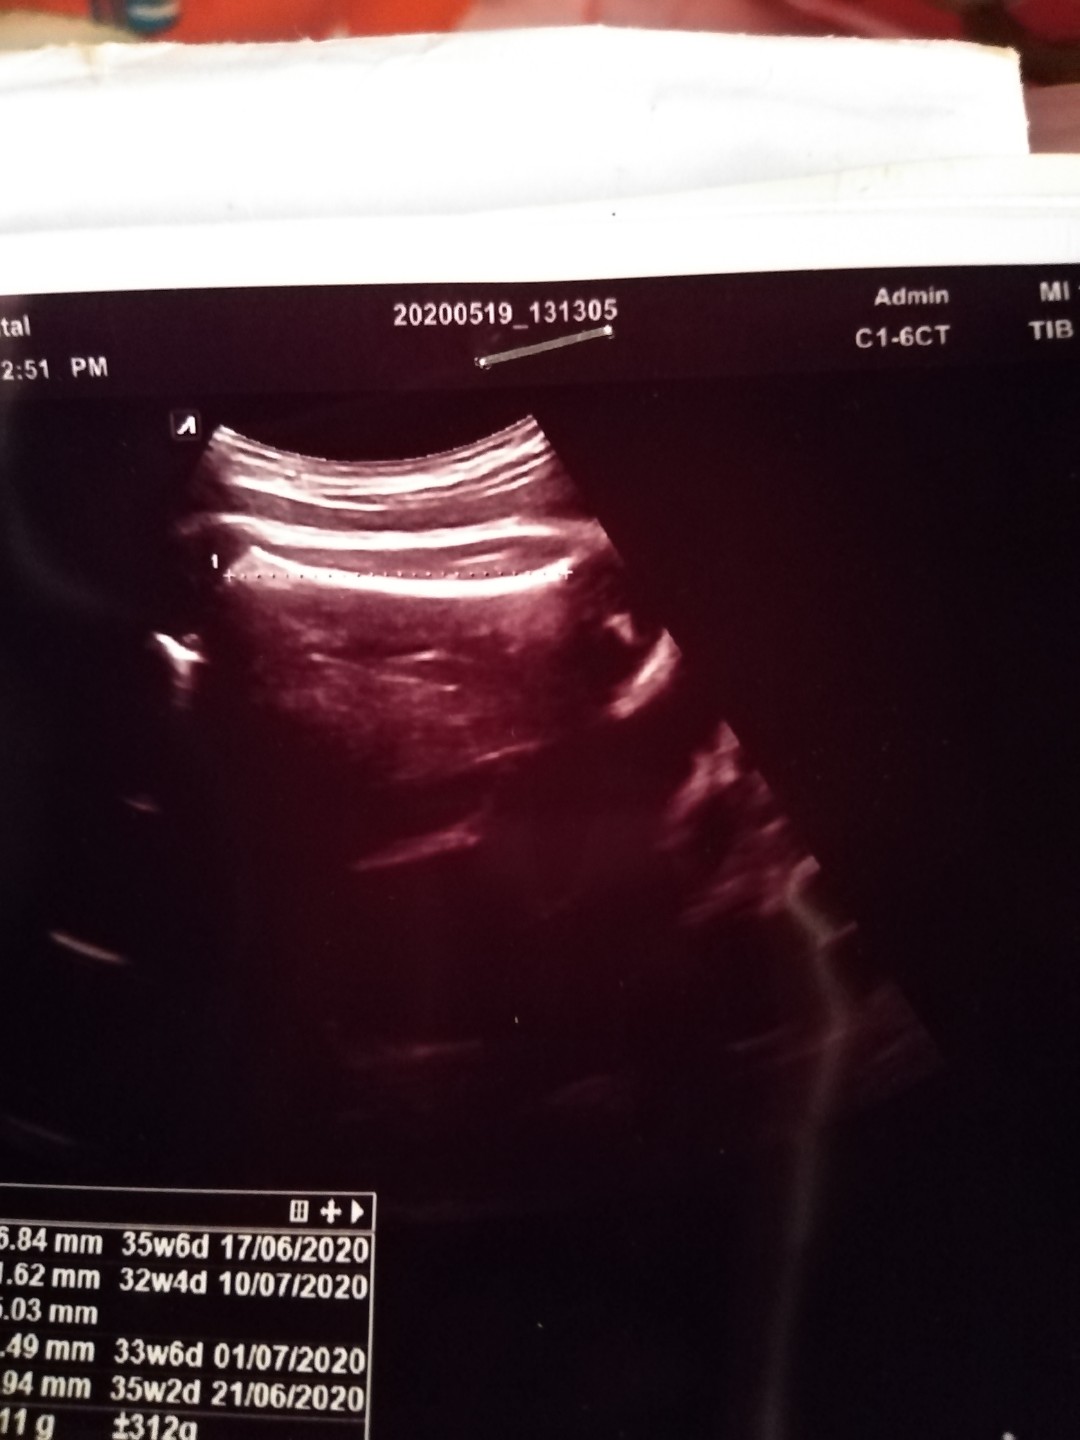

ช่วยดูให้หน่อยนะคะ...ว่าเพศไหน...ดูว่าผลอัลตร้าซาวด์ชัวไหม

หมอบอกเพศหญิงคะ

ขออนุญาติน้ะค้ะ แม่ๆคนไหนดูออกบ้างไหมคะว่าในภาพคืออะไร หมอไม่บอกอะไรเลยค่ะซาวด์ตอน36วีค

ภาพไม่ชัดค่ะ มองไม่ออกเลย เชื่อหมอนะคะ

หมอบอกว่าผู้หญิง80%คะ... รอซาวด์อีกครั้งตอน7เดือนเผื่อความชัวคะ